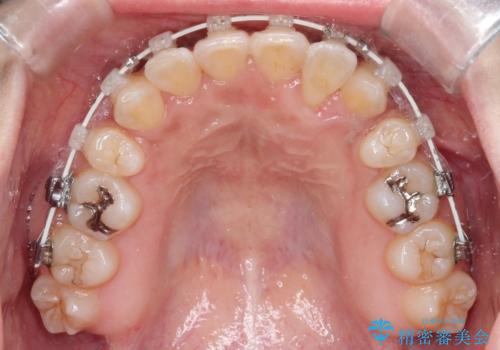

- 患者様は、歯並びのガタガタ(重度の叢生)を改善したいとのことで来院されました。診察すると、歯列のスペース不足が著しく、前歯が重なり合い、噛み合わせにも影響が出ている状態でした。歯をきれいに並べるためには抜歯によるスペース確保が不可欠と判断し、上下の小臼歯4本を抜歯したうえで、目立ちにくい審美ワイヤー矯正(白いワイヤーと透明ブラケット)を用いた治療計画を立てました。

抜歯によって歯を動かすためのスペースを確保。その後、審美ワイヤー矯正を用いて歯を1本ずつ適切な位置に誘導しながら、噛み合わせのバランスも整えていきました。時間はかかりましたが、ガタガタの歯並びがきれいに整い、機能的にも審美的にも満足のいく仕上がりとなりました。患者様からは「歯並びが劇的に改善し、見た目だけでなく噛みやすさも向上した」と喜びの声をいただきました。